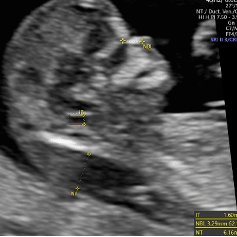

Nackenfaltenmessung/Nackentransparenz

Als „Nackentransparenz“ wird ein Flüssigkeitsraum unter der Haut des Nackens bezeichnet. Dieser lässt sich im ersten Trimester mittels hochauflösenden Ultraschalls messen. Ist diese auffällig dick, kann dies ein Hinweis für Auffälligkeiten der Chromosomen, wie z. B. der Trisomie 21 sein. Mittlerweile weiß man, dass auch viele andere Erkrankungen zu einer Erhöhung der Nackentransparenz führen können, wie z. B. Herzfehler, Skelettauffälligkeiten und viele andere Fehlbildungen und genetische Störungen. Die Messung der Nackentransparenz ist also ein wichtiger Hinweis für ein breites Spektrum an Krankheiten und sollte durch eine frühe Feindiagnostik mit Herzbeurteilung ergänzt werden. Alles zusammen bildet die Basis, um über weitere mögliche Diagnostik sinnvoll zu entscheiden.